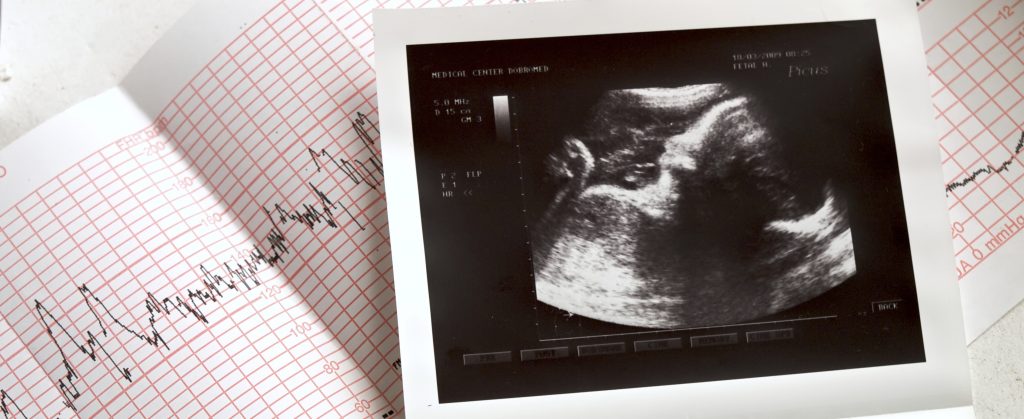

UNC CMIH provides high-quality and cutting-edge therapies to high-risk pregnant women and their babies. Our coordinators provide comprehensive care to women, infants and their families from diagnosis through decisions and delivery.

An expert team of maternal fetal medicine specialists, pediatric surgeons, neonatologists, and pediatric specialists have worked together for decades at UNC to provide high-quality and cutting-edge therapies to high-risk pregnant women and their babies. The Center provides comprehensive care to women, infants and their families from diagnosis through decisions and delivery. To learn more about our program, please click here to view our fetal care website.